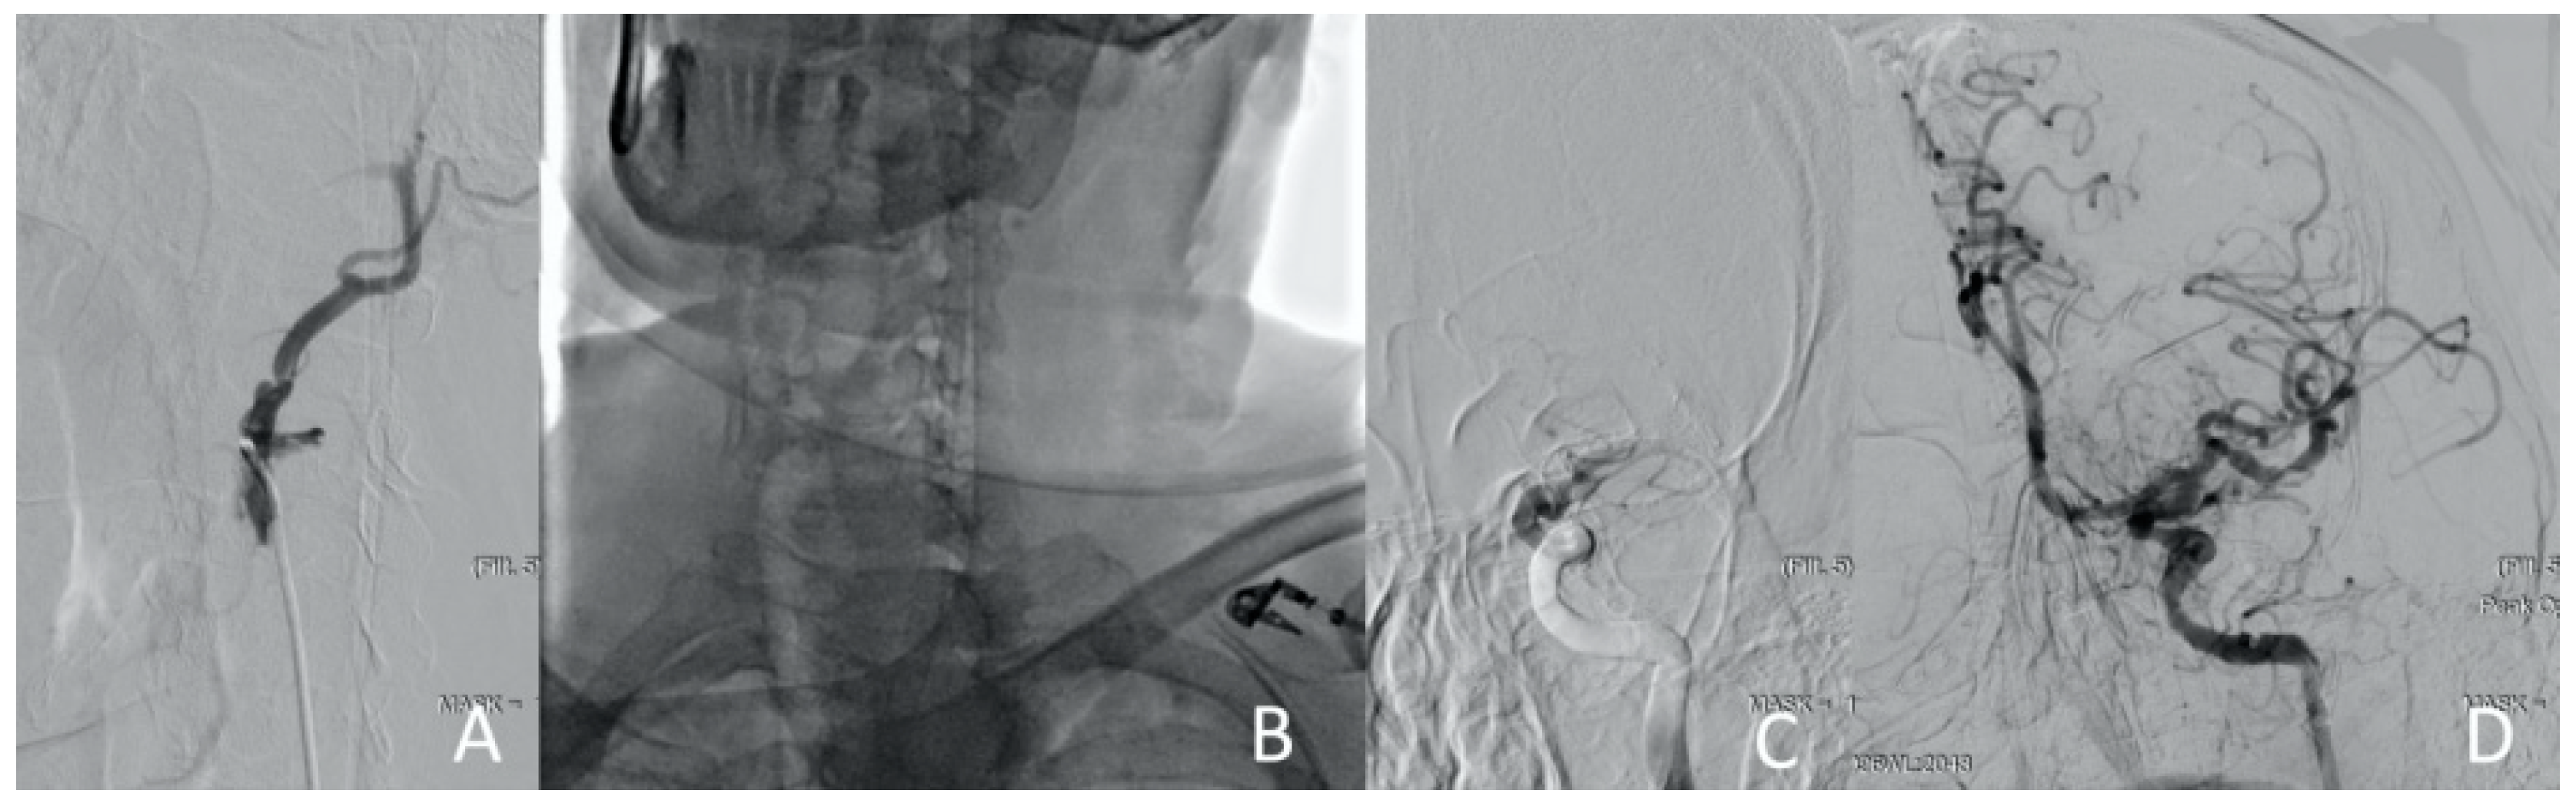

Figure 4.

Clinical Case 1, Patient M., 73 years old. Results of the angiography: (A) brachiocephalic and subclavian artery angiography via radial access; (B) left common carotid artery angiography, a low contrast defect is visible throughout; (C) left subclavian angiography. A contrast defect is visible throughout the artery.

After the emergency examination by the cardiac surgeon and neurologist, a decision of carotid revascularization and stenting was performed. Through the right common femoral artery, with no technical difficulties, the revascularization of the left common carotid artery (CCA) by the implantation of three self-expending carotid stents into the left internal carotid artery (ICA) and CCA was performed (Figure 5).

Figure 5.

Clinical Case 1, Patient M., 73 years old. Results of the angiography: (A) left ICA stenting with the first stent; (B) CCA stenting with a second stent; (C) CCA stenting with the third stent. The arrows indicate contrast defects that persist after stenting (compression of the true lumen).

The left hemisphere blood flow was restored at the level of TICI-III. However, repeated attempts to cannulate the right CCA were unsuccessful due to orifice compression. It was decided to perform the retrograde recanalization of the right ICA and CCA through the anterior connective artery (ACA). Subsequently, the guide catheter of 0.014 Fr was (doubtful) withdrawn into the aorta, captured using a loop trap, and externalized via radial access (Figure 6).

Figure 6.

Clinical Case 1, Patient M., 73 years old. Results of the angiography: (A) conducting the guide catheter through the ACA and further into the ICA; (B) the moment of capturing the guide catheter from the radial artery; (C) right ICA angiography using the diagnostic catheter via radial access.

The right ICA and CCA were also stented using the peripheral self-expending stent 6.0 × 150 Innova Boston Scientific via radial access. Cerebral circulation was totally restored. The time from symptom onset to left and right hemisphere revascularization was 55 and 150 min, respectively (Figure 7).

Figure 7.

Clinical Case 1, Patient M., man, 73 years old. Full metal jacket of both sides’ carotid arteries.